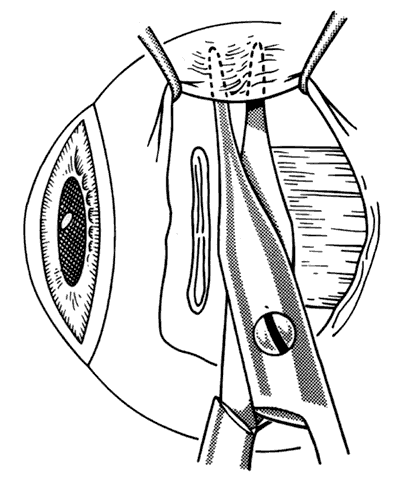

If a muscle tendon has been split during mobilization of the tendon or by passing a muscle hook under a scarred tendon, the marginal myotomy should be avoided. Placing cuts in the muscle may cause the muscle to be transsected (Figs. 37 through 40).

Fig. 37. When a muscle is split, a marginal myotomy is contraindicated.

Fig. 38. The split muscle is clamped.

Fig. 39. The cuts in the muscle divide it.

Fig. 40. The muscle can retract into the orbit.